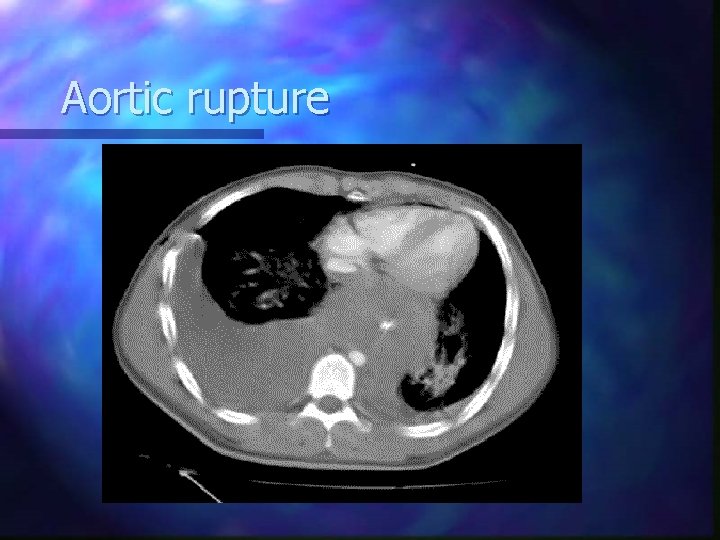

Aortic rupture Usually blunt trauma involving deceleration forces; n ~90% die within minutes n Most common site near ligamentum arteriosum n Treat like an aneurysm if still alive, blunt trauma VSA if dead (? pronounce) n Rx: surgical…poor prognosis n

Aortic rupture